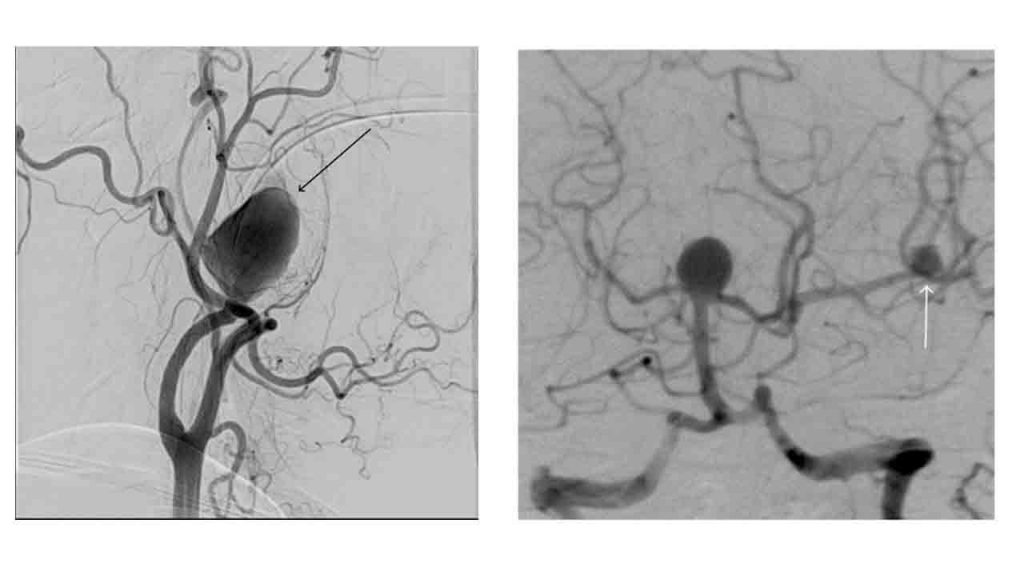

Endovasküler embolizasyon yani anjiografik tedavi diğer tedavi seçeneğidir. Hasta uyuşturulduktan sonra, Girişimsel Radyolog içi boş bir plastik tüpü (kateter) bir artere (genellikle kasık yoluyla) sokar ve bunu X-ışını kontrolü altında vücuttan anevrizma bölgesine doğru ilerletir. Bir kılavuz tel kullanılarak metal bobinler (koil dediğimiz) kullanılarak (A), stent kullanılarak (D) veya birçok durumda bunların birlikte kullanımı ile (C) anevrizmaya kan girmesi engellenir/kısıtlanır ve kanama önlenir.

Bu teknikle ilgili klinik deneyimin artması ve malzeme tasarımındaki gelişmeler, cerrahi klipsleme ile tedavi edilebilecek hastalarda bile anevrizma embolizasyonunun kullanımının giderek artmasına yol açmıştır. Artık birçok merkezde cerrahi tedavi yalnızca hastanın öncelikli olarak endovasküler tedavi ile tedavi edilemediği durumlarda kullanılmaktadır.